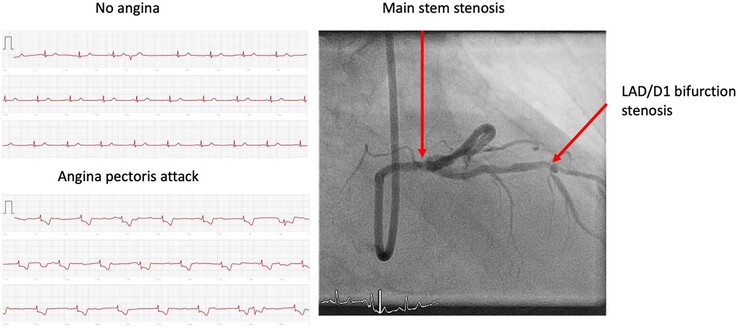

Aufgrund der mittels ECG-Funktion der Apple Watch 5 aufgezeichneten Daten, die auf schwere Durchblutungsstörungen (Ischaemia) des Herzens deuteten, wurde die Patientin allerdings sofort ins Katheterlabor gebracht, wo eine Stenose (Verengung der Blutgefäße) festgestellt und mittels Stents behoben wurde. Am Tag darauf konnte die Dame das Spital wieder verlassen.